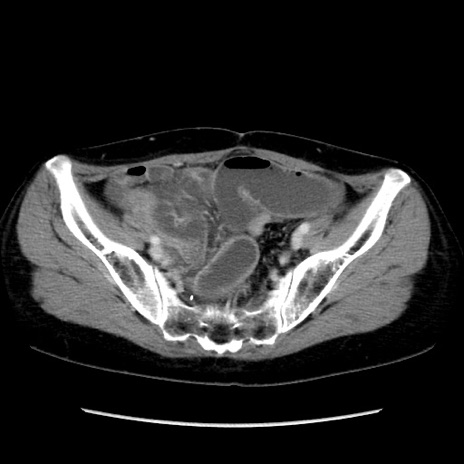

冠状断像

矢状断像